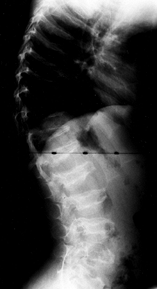

as a “champagne glass” appearance. The radiographic hallmark of the

achondroplastic spine is progressive narrowing of the transverse

interpedicular distance as one measures from cephalad to caudad in the

lumbar spine (Fig. 180.3). The pedicles are thickened, and there may be posterior scalloping of the vertebral bodies.

![]() |

|

Figure 180.3. Progressive interpedicular narrowing in the lumbar spine of a 5-year-old girl with achondroplasia.